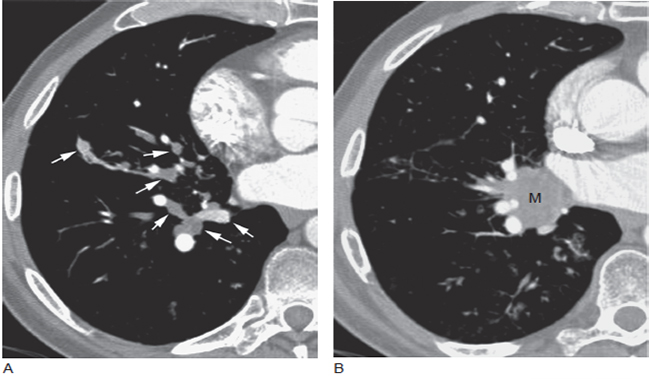

图8 肺癌支气管阻塞患者的黏液栓

A. 下叶支气管充满黏液栓(箭头),充满黏液的支气管位于肺动脉旁,远端的肺组织保持充气; B. 更高层面显示肺门肿块(M) 伴右肺下叶支气管阻塞